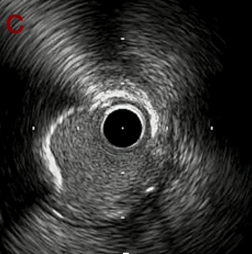

IVUS after OAS high speed 3回追加

IVUS imaging after high speed 3回追加

a,b,cの十分な石灰化のsanding。

High riskのbias所見へと変わっていったdの部位に関してはpinpoint OASを行うことでinjuryなく治療できた。